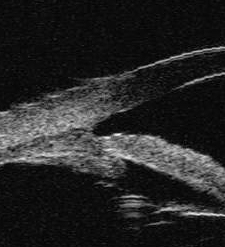

Figure 10 of Yu, Mol Vis 2012; 18:1074-1082.

Figure 10. The group A show the chamber angle are opening at 12 month after operation (in terms of UBM).